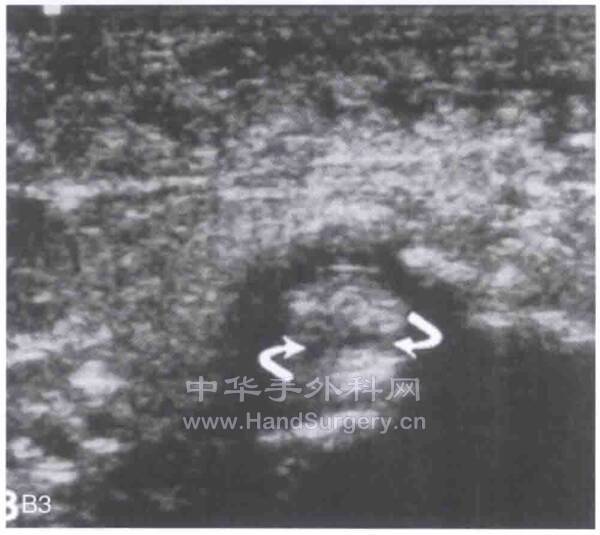

正常人胫后肌腱直径为4-6mm,腱鞘炎的成像是肌腱周围有大量的液体回声区

在纵向声波图中见低回声区或者在横向声波图中见靶信号是胫骨后肌腱腱鞘炎的特征性表现

这里的“靶信号”是一个专业术语,即用来描述被液体低回声区包绕的、呈连续均匀高回声区的肌腱

包绕肌腱的低回声光环区域即表示周围存在过多积液